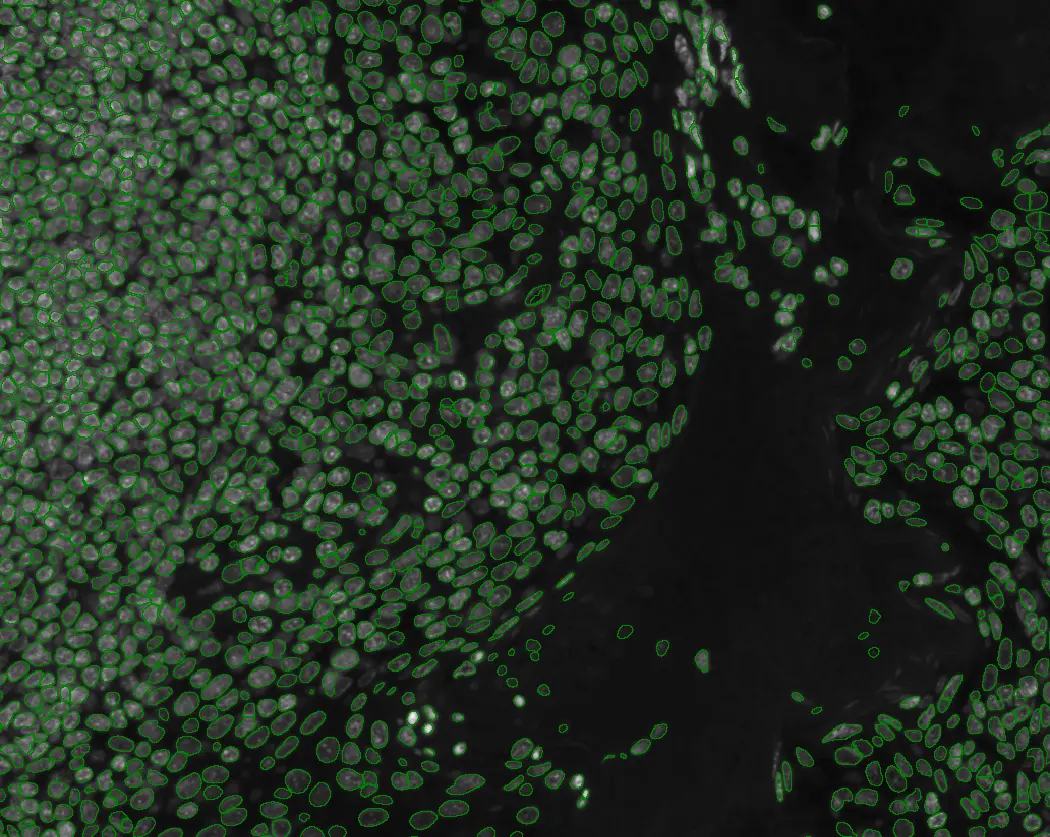

Quantitative Analysis of Cultured Cells: High-End Solution for Ready-To-Publish Data

A case study using StrataQuest image analysis on IF-processed cultured cells. The workflow automated cell identification, nuclei and cytoplasm counting, and marker intensity quantification.